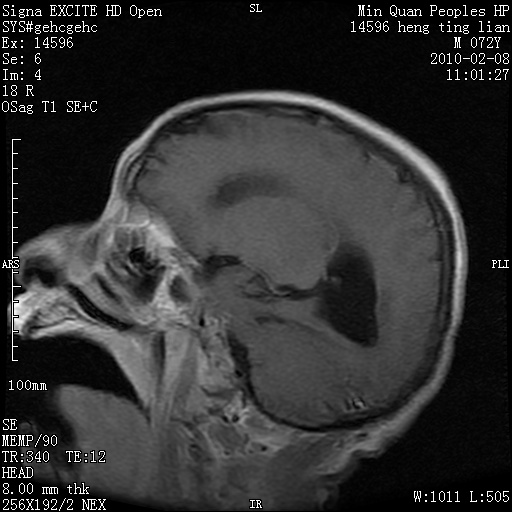

m,72,头疼,头晕两年,伴视力模糊三月,饮食呛咳两天。pe:颈部抵抗,左眼突出,左眼瞳孔约3mm,对光反射消失,双眼失明,伸舌困难,双肺呼吸音粗,心率110次/分,左上肢肌力i级,左下肢屈曲,肌张力高。现有08年2月19mri平扫及10年2月8日mri增强请会诊。ct病灶呈低密度伴散在点、片状等密度区,无明确钙化(无ct片资料可供上传)。[

脑外肿瘤,囊实性,环状不规则强化,内听道扩大,考虑神经源性肿瘤

左侧桥小脑区占位伴梗阻性脑积水----考虑 1神经鞘瘤 2室管膜瘤。

左侧桥小脑区神经鞘瘤伴梗阻性脑积水。

脑外肿瘤,病灶呈匍匐蔓延,表皮样囊肿可能性大。